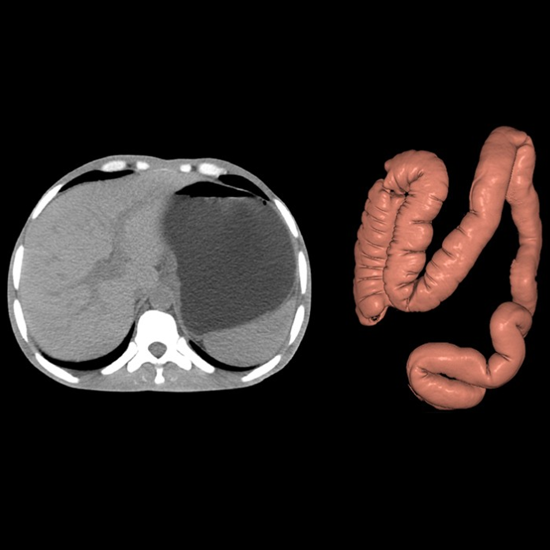

Anatom 64 Clarity, kardiyak görüntülemede giriş seviyesindeki rakiplerine oranla daha düşük doz ile daha yüksek kaliteli görüntüler sunan teknolojik donanımlara sahip 64 kesit bir bilgisayarlı tomografi sistemidir.

Yüksek zamansal çözünürlük sunarak kullanıcı deneyimini iyileştiren Anatom 64 Clarity, aynı zamanda 5.3 MHU'luk tüpü sayesinde 120 saniyeye kadar devamlı çekim imkanı sunar ve tüm gün çekimlerde herhangi bir sorun yaşanmamasına olanak tanır.

Görüntü bozulmalarını engelleyecek yazılımlara sahip olan Anatom 64 Clarity, farklı klinik ihtiyaçlara uyum sağlayabilmesi için dijital ve mekanik eğim ayarlarına sahiptir ve gerçek zamanlı çarpışma önleme sistemleriyle hasta güvenliğini de sağlar.